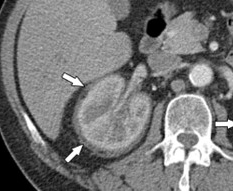

腹部造影CT(平衡相)

両側腎盂に壁肥厚を認める。

<後腹膜病変>

• 水腎症・尿管拡張(33%)

• Hairy kidney(68%)